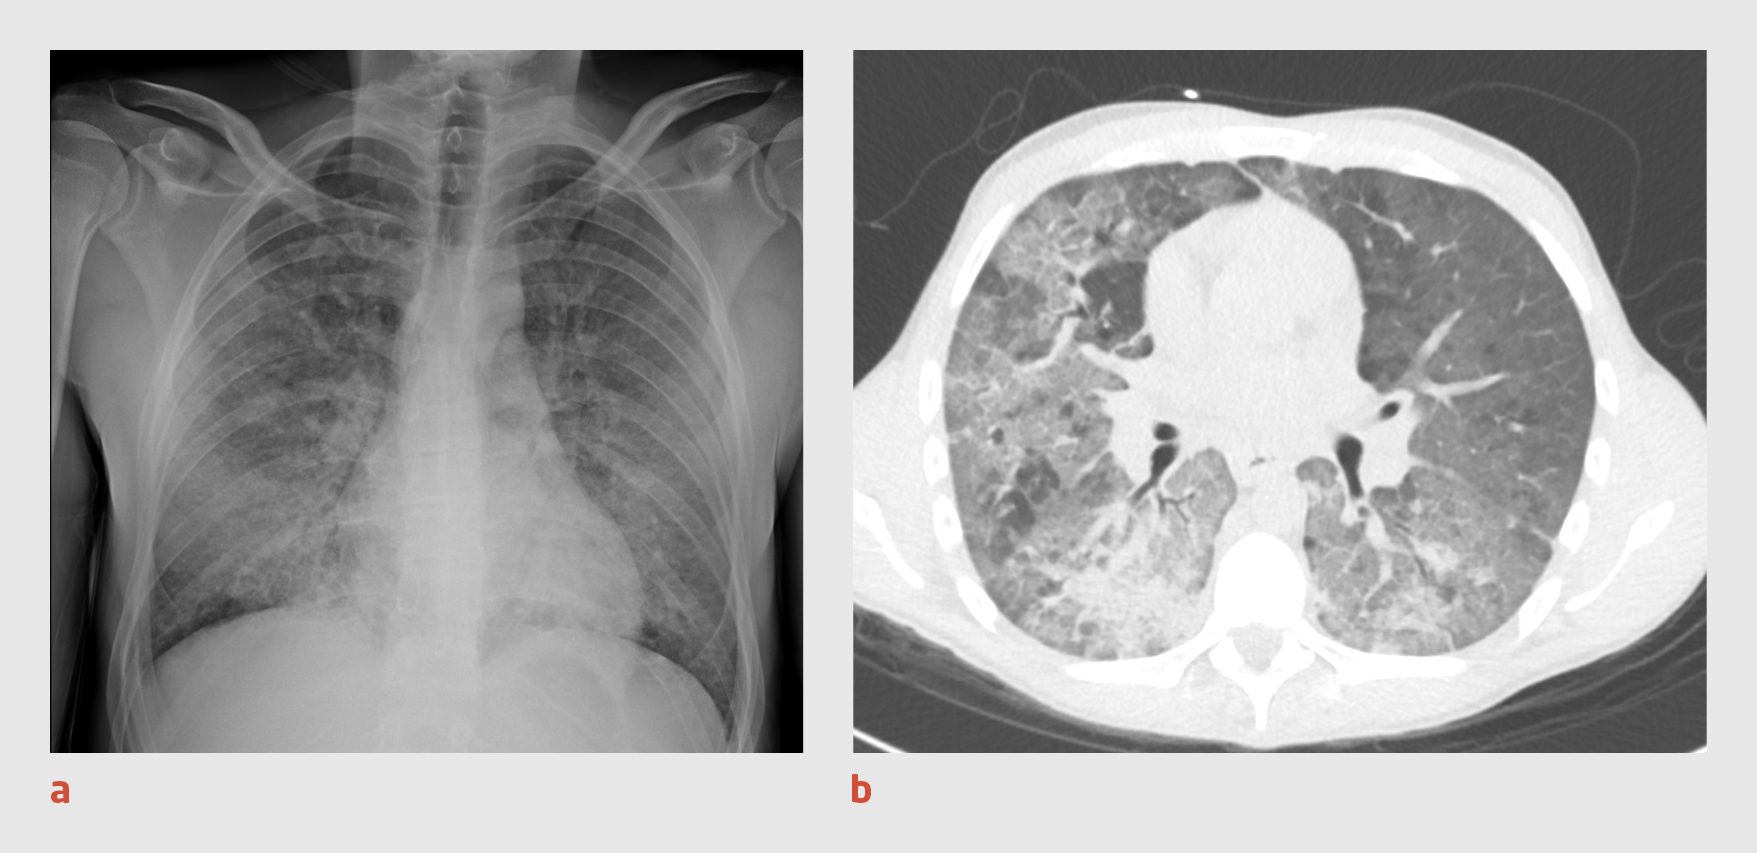

Patiënt C, een 71-jarige vrouw met hypertensie, bezoekt de Spoedeisende Hulp, omdat zij sinds enkele weken toenemend hoest en vermoeid is. Zij is niet kortademig en heeft geen koorts gehad. Bij lichamelijk onderzoek zien wij een niet-acuut zieke vrouw met een zuurstofsaturatie van 98%, terwijl zuurstof wordt toegediend met 2 l/min. Zij heeft een polsfrequentie van 154 slagen/min, wat blijkt te berusten op atriumfibrilleren de novo. Bloedonderzoek geeft onder meer de volgende uitslagen: leukocytengetal: 16,9 x 109/l (4-10); lymfocytengetal: 0,55 x109/l; CRP: 243 mg/l; kreatinine: 165 μmol/l (< 90); en LDH: 313 U/l. De thoraxfoto toont uitgebreide consolidaties in beide longen (figuur 3a). Patiënte wordt opgenomen in strikte isolatie onder de werkdiagnose ‘covid-19’.

Figuur 3

Thoraxfoto en CT-thorax van patiënt C

Figuur 3 | Thoraxfoto en CT-thorax van patiënt C

(a) Thoraxfoto van een 71-jarige vrouw waarop in beide longen uitgebreide consolidaties te zien zijn. (b) Op de CT-scan van de thorax zijn uitgebreide peribronchovasculaire matglasafwijkingen met scherpe contouren (‘crazy paving’) en grillige consolidaties zichtbaar, overeenkomstig een CO-RADS-score van 5.

Er wordt een PCR-test verricht op SARS-CoV-2 in materiaal uit de nasofarynx en patiënte wordt intraveneus behandeld met ceftriaxon 2 g 1 dd. Ook krijgt zij digoxine voorgeschreven vanwege het nieuw ontstane atriumfibrilleren. Het urinesediment bevat 10-50 leukocyten/μl (< 10), > 150 erytrocyten/μl (0) en natrium 14 mmol/l (geen referentiewaarde, omdat de urinenatriumconcentratie onder andere wordt bepaald door het dieet). De nierinsufficiëntie wordt geduid als ‘prerenaal’ en passend bij een slechte vochtinname. Patiënte krijgt NaCl 0,9% 2 l/h toegediend per infuus. De volgende dag blijkt de uitslag van de PCR-test negatief te zijn. Omdat wij op basis van het klinische beeld nog steeds een vermoeden van covid-19 hebben, wordt CT-onderzoek van de thorax verricht. Op de CT-scan worden uitgebreide peribronchovasculaire matglasafwijkingen gezien met scherpe contouren (‘crazy paving’; CO-RADS-score 5) (figuur 3b); deze afwijkingen passen niet alleen bij covid-19, maar ook bij een P. jiroveci-pneumonie of een auto-immuunpneumonitis. Met een PCR-test konden in de bronchoalveolaire lavagevloeistof geen verwekkers, zoals SARS-CoV-2 of P. jiroveci, aangetoond worden. Vanwege het vermoeden van auto-immuunpneumonitis worden de concentraties van antinuclaire antistoffen (ANA) en antistoffen tegen het cytoplasma van neutrofiele granulocyten (ANCA) in het bloed bepaald.